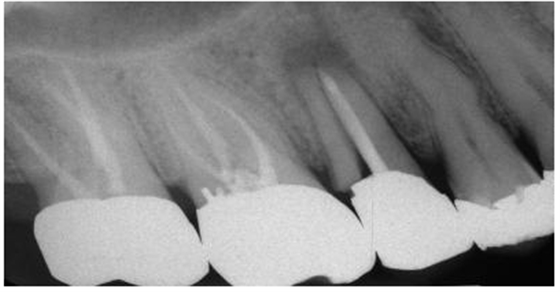

圖1:上頜第二前磨牙根折的根尖片,經(jīng)由預(yù)成金屬樁修復(fù)

盡管短樁從未被提倡使用,但是研究發(fā)現(xiàn)經(jīng)常能在根尖片上觀察到短樁的存在(圖 3)。臨床上發(fā)現(xiàn)在327例樁修復(fù)當(dāng)中,僅僅有34%的樁長(zhǎng)度與冠上切-頸長(zhǎng)度相當(dāng),即冠與樁長(zhǎng)度的比例為1:1。一項(xiàng)研究曾對(duì)200例牙髓治療后的牙齒進(jìn)行評(píng)估,結(jié)果顯示僅僅14%的樁長(zhǎng)度為牙根長(zhǎng)度的2/3或者長(zhǎng)于牙根長(zhǎng)度的2/3。另外一項(xiàng)根尖片研究結(jié)果表明樁修復(fù)中,樁長(zhǎng)度為牙根長(zhǎng)度的2/3或者3/4的比例僅占5%。當(dāng)臨床上應(yīng)用短樁修復(fù)時(shí),由于高應(yīng)力的原因,牙根常常會(huì)發(fā)生折斷,反之,增加樁的長(zhǎng)度能夠提高牙根的抗折能力。